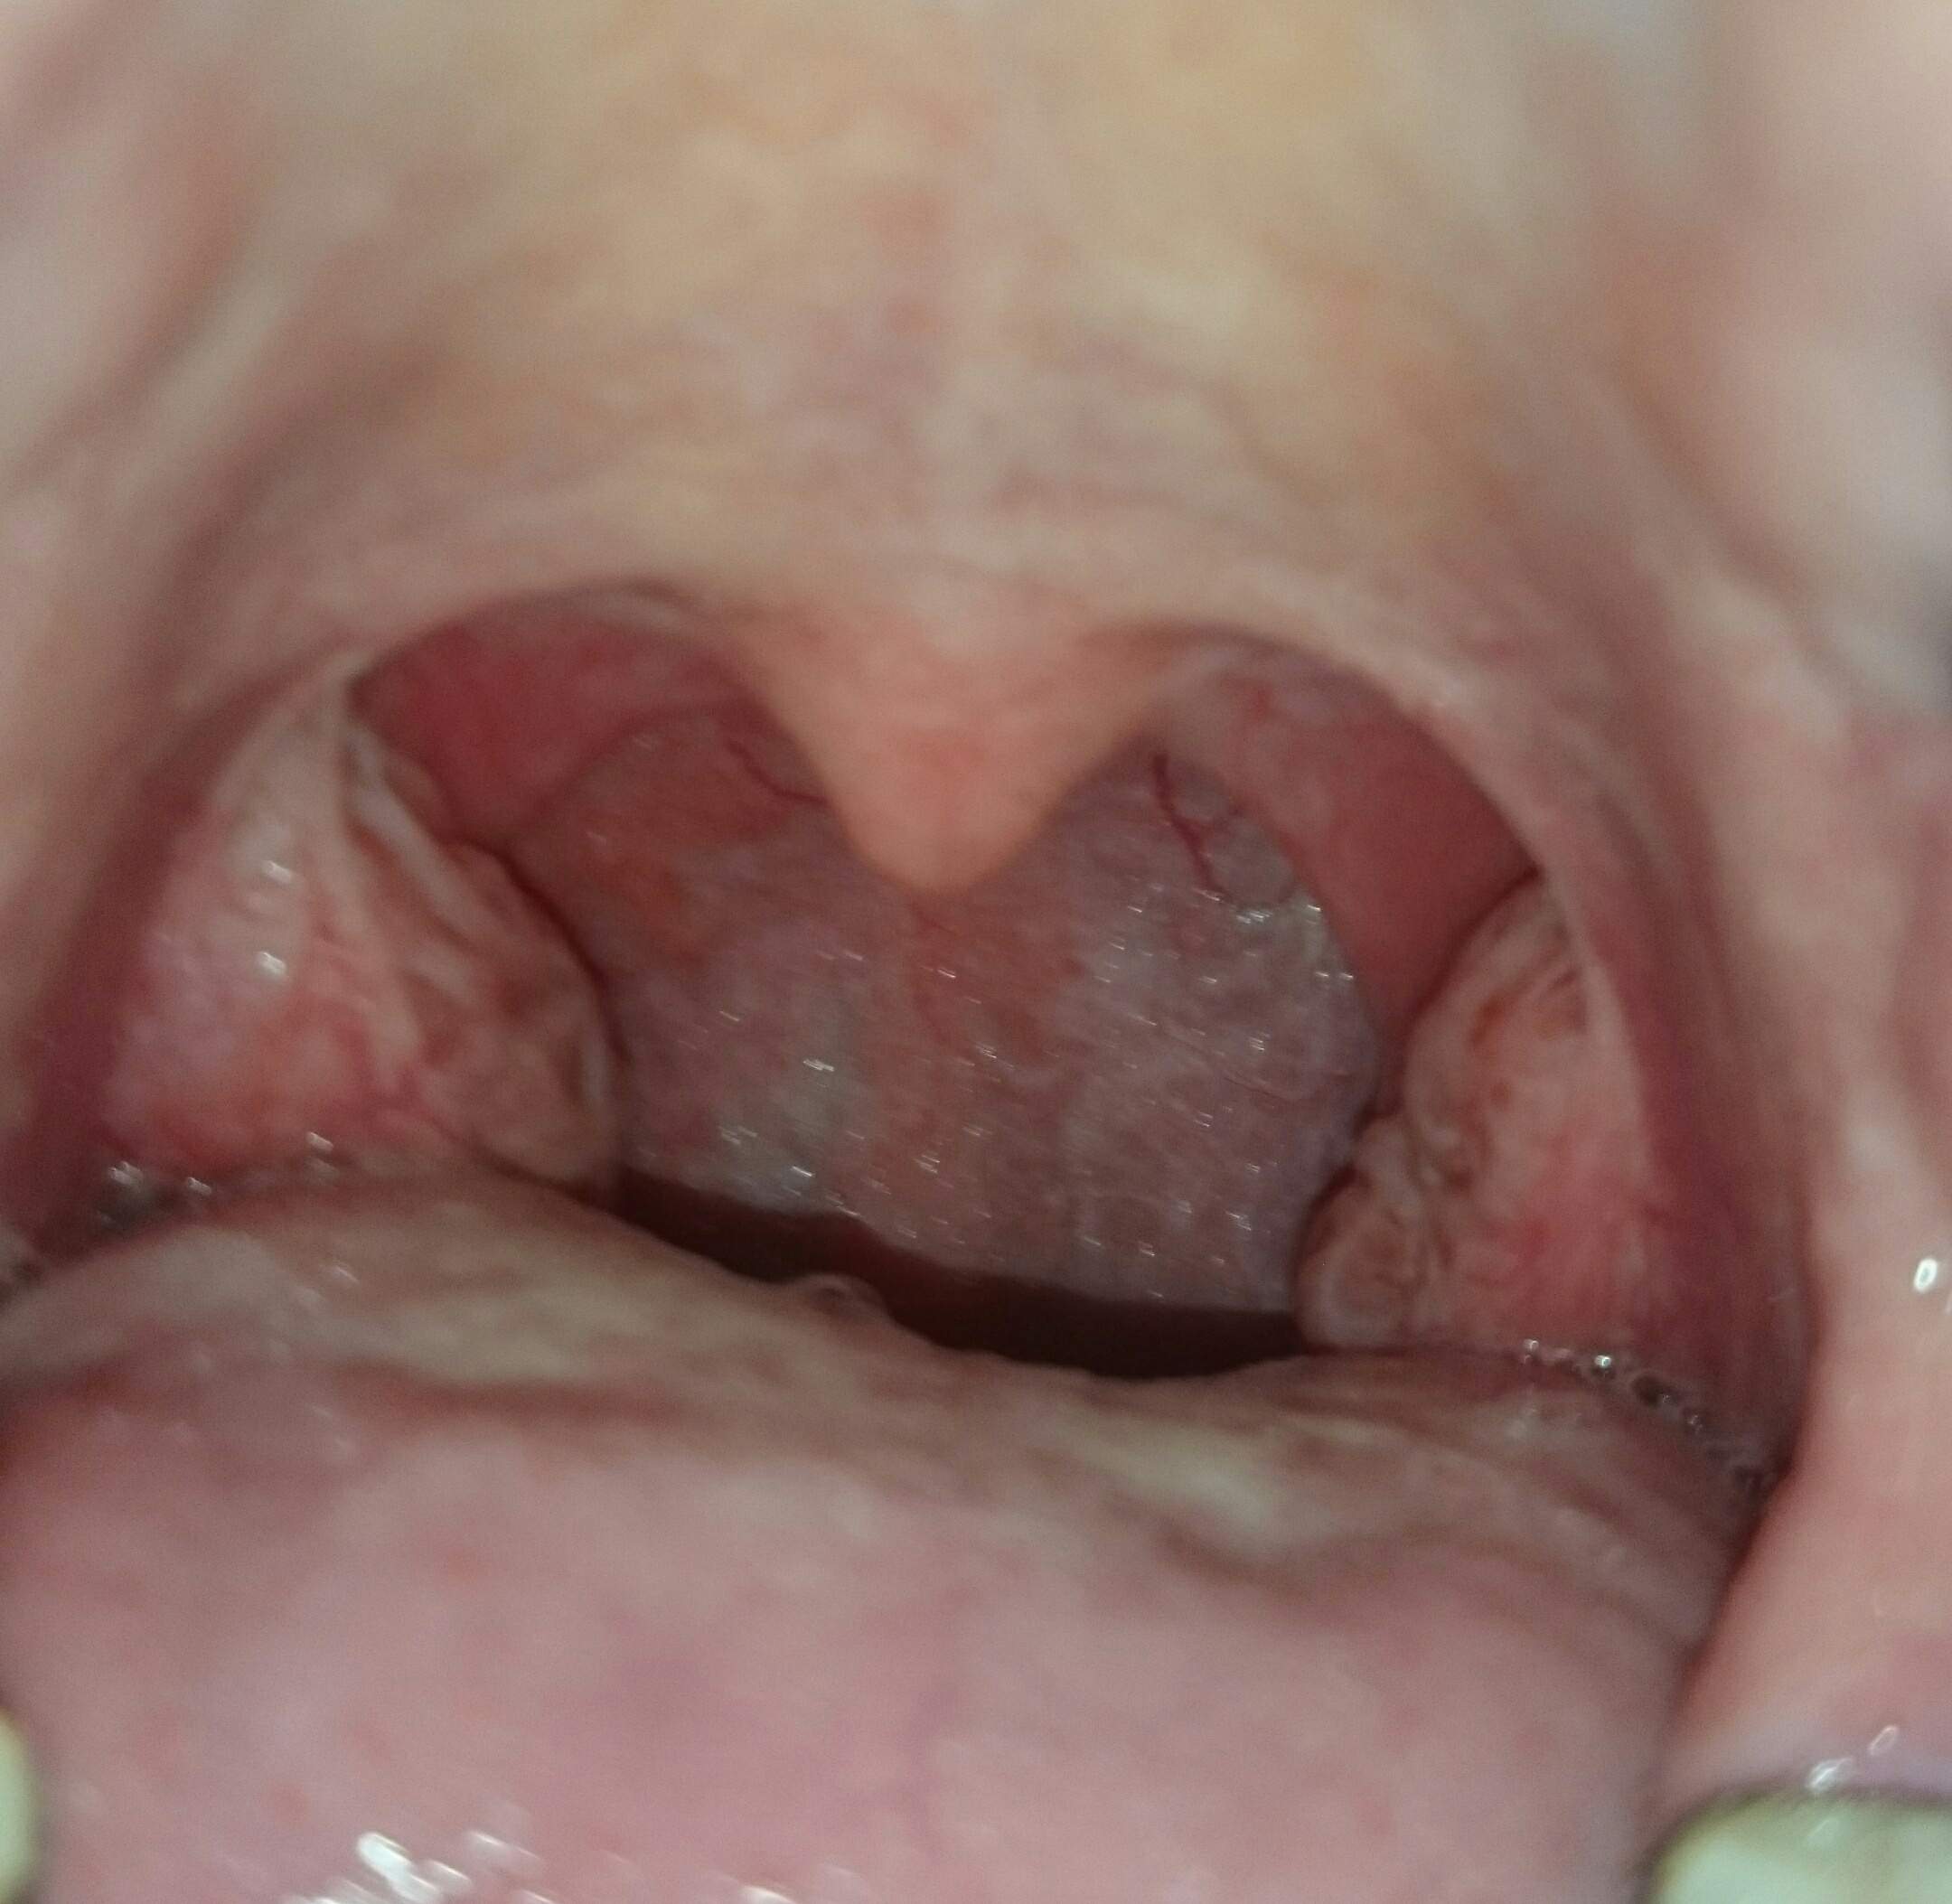

Vergrößerte Rachenmandel

Beim Fehlen dieser Mandeln haben Erreger wesentlich freieren Zugang zum Rachenraum. Es gibt zwei Formen der Mandeloperation: Zum einen kann man die Gaumenmandeln komplett entfernen (Tonsillektomie), eine Maßnahme, die vor allem bei Kleinkindern mit chronischen Mandelentzündungen sowie bei älteren Kindern, Jugendlichen und Erwachsenen zum .Die Rachenmandel ist dabei nicht so tief zerklüftet wie die beiden Gaumenmandeln und spielt auch für das Immunsystem keine so wichtige Rolle wie ihr „großen Schwestern. Wird die vergrößerte Rachenmandel entfernt, hat dies keine . Die Tonsillektomie (Mandelentfernung) ist eine Operation, bei der die Gaumenmandeln vollständig entfernt werden. Vergrößerte Rachenmandeln können die Stimme jedoch näselnd klingen lassen (d.Gaumenmandeln, Rachenmandeln entfernt, Husten und Brechreiz normal? Guten Abend, Mein Sohn wurde am 12. Die Rachenmadeln zu entfernen dauert etwa zehn bis 15 Minuten. Normalerweise dauert es 1-2 Wochen, aber manchmal kann es auch länger dauern. Dadurch kann es auch nach Jahren erneut zu einer Mandelentzündung kommen. Wenn Sie neugierig sind . Daher wird im Untersuch festgestellt, ob eine Entfernung (Adenotomie) angeraten ist. Spanne oder biege deine Halsmuskeln, während du deine Zunge herausstreckst. Deshalb operiert man die Rachenmandel im Gegensatz zu den Gaumenmandeln auch schon bei Kleinkindern, die meisten Operationen werden .Denn wenn man vergrößerte Rachenmandeln (oft auch Polypen genannt) früher entfernt, können sie wieder nachwachsen. Wenn ein Kind dauerhaft unter einer vergrößerten Rachenmandel leidet, entscheiden sich viele Ärzte für eine Entfernung. Die wuchernde Rachenmandel verschließt die Öffnung zur Nasenhöhle hin und behindert damit die natürliche Nasenatmung. Sprechen wir von „Mandeln“, sind die Gaumenmandeln gemeint.Viele Eltern entscheiden sich für den Besuch beim Hals-Nasen-Ohren-Arzt, der gerade bei Kindern im Alter zwischen zwei und fünf Jahren oft eine Vergrößerung der Rachenmandel feststellt.

Vergrößerte Rachenmandeln (Adenoide) können den Nasen-Rachen-Raum zum Teil oder vollständig verlegen. Lebensjahr nicht mehr. stark näselt, das Kind immer wieder unter fieberhaften Infekten der oberen Atemwege leidet,

So überwachen sie alle Zugänge der Körpers im Bereich des Kopfes. Bei Kindern mit vergrößerten Rachenmandeln kann der Gaumen auffällig geformt sein und die Zähne können eine . Obwohl es sich bei der Entfernung der Rachenmandeln um einen einfachen Standardeingriff handelt, gibt es verschiedene Risiken der Adenotomie. Das Schlucken fällt schwer und an Essen ist kaum zu denken: Eine Mandelentzündung tut höllisch weh. Umgangssprachlich wird eine Rachenmandelwucherung häufig als . Behandlung: Abschwellen mit kortisonhaltigen Sprays, seltener Kortison in Tablettenform, operative Entfernung per Endoskop, zum Teil per Laser; Hausmittel: Dampfinhalation oder Nasenspülung.Die Rachenmandel wird mit speziellen Instrumenten vom Rachendach entfernt. Im übrigen ist eine operative Entfernung der Adenoide aber ohnehin nur in Ausnahmefällen notwendig. Je nach Lage und Ausmaß der Vergrößerung kann es zu folgenden Symptomen kommen: behinderte Nasenatmung. Eine Tonsillotomie ist ein Verfahren, bei dem Chirurgen die meisten . Ärzte führen sie meist dann durch, wenn die Mandeln sehr oft entzündet sind oder die Atemwege einengen. Nein,die Mandeln wachsen nicht nach. Grundsätzlich .Ungefähr bis zum sechsten Lebensjahr ist das Immunsystem noch am Wachsen. Die Entfernung der Rachenmandel wird als Adenotomie bezeichnet.Mandelsteine entfernen. Häufig kommt es zu einer krankhaften Vergrößerung (Hyperplasie) der Rachenmandel, meistens zwischen dem 2. Den Rachenmandeln kommt im Körper eine wichtige Bedeutung für das Immunsystem zu. Sie schnarchen dann zum Beispiel nachts vermehrt, häufig kommt es zu Problemen im Mittelohr. Symptome: Eingeschränkte Nasenatmung, Schnarchen, häufige Infektionen, näselnde Stimme, Verlust von Geruchs- und Geschmackssinn.